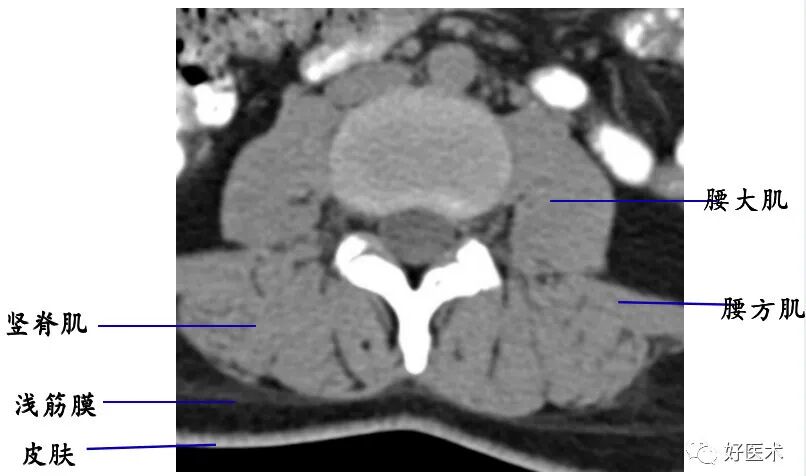

1. 经椎弓根的横断层面:

断面经过的部位:椎弓根

主要特征:椎管为完整性骨环,由椎体、椎弓根和椎弓板构成

椎旁软组织:CT上均表现为软组织密度结构,CT值约40HU~50HU